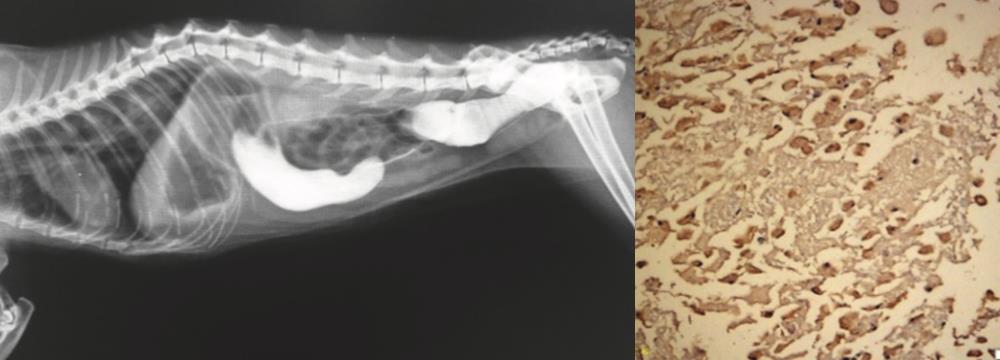

Read moreGiriş Tüm kedi neoplazilerinin yaklaşık %1’ini nazal boşluk ve paranazal sinusların tümörleri oluşturur. Bu oran son çalışmalarda %8.4 civarında bildirilmiştir....